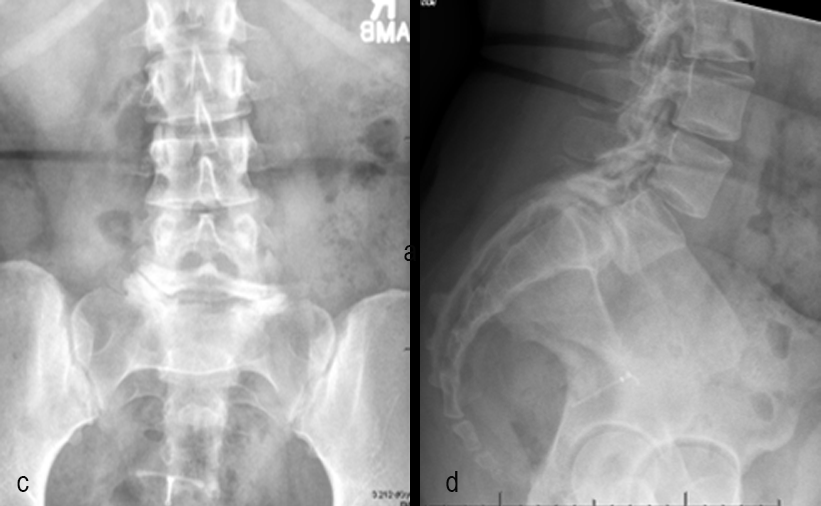

A 17-year-old girl presented to the spine clinic with significant low back pain. X-ray, CT and MRI imaging (Figs 1-3) showed evidence of spondylolisthesis. Upon clinical examination of spinal alignment, the patient was found to have a pelvic incidence of 78°, a lumbar lordosis of 54°, and a pelvic tilt of 51°.

Posterior spinal instrumentation and fusion (PSIF) was undertaken with an interbody fusion at L5-S1. L5 laminectomy and sacral dome osteotomy followed by pedicle screw instrumentation using TriALTIS™ implants helped reduce the lumbosacral kyphosis and translation of L5-S1 and promote fusion across this level (Fig 4a-b).